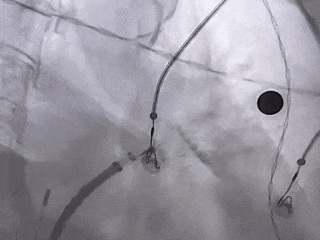

压缩比测量

压缩比17.3%,在10%-30%之间,符合推荐压缩比

Lefort封堵器评估符合PASS原则,释放封堵器,封堵器位置稳定且未见残余漏,封堵完美。

正足位

肝位

ICE